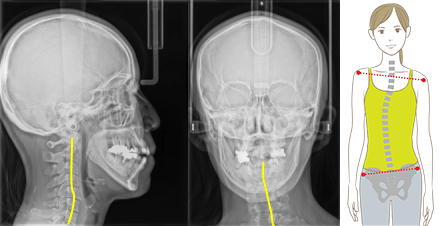

足の長さのずれは整体で治りますが、次の日にはまた戻ってしまいます。

しかし、整体された状況下で顎の位置の記録をとることで、姿勢は崩れにくくなります。